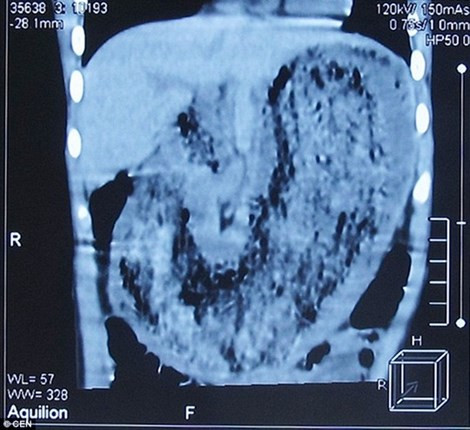

Tại bữa ăn trong Tết Nguyên đán mới đây, bé gái ngã bệnh nên người cha đã đưa con đến các bác sĩ. Sau khi khám tổng quát, một bác sĩ tại địa phương phát hiện vật lạ giống khối u trong bụng bệnh nhi. Kết quả chụp CT cho thấy trong dạ dày bị lấp đầy bởi một vật lạ nhưng vị bác sĩ chưa kết luận chính xác đó là gì.

Ảnh chụp cho thấy khối tóc trong dạ dày bệnh nhi

Ngày 27/3, bệnh nhi được phẫu thuật thành công và đã được xuất viện trong tuần này. Các bác sĩ lấy ra từ dạ dày bé gái một búi gồm tóc, sợi quần áo, bao bì… nặng gần 2 kg. Búi tóc được kết với nhau khá chặt do tồn tại trong nhiều năm qua, có hình dạng như chiếc dạ dày và ngăn cản việc tiêu hóa thức ăn.